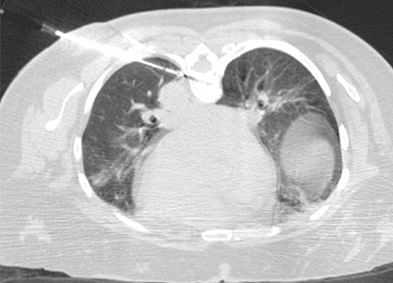

Cryoablation of mCRC in the Lung Located Adjacent to the Aorta

A 57-year-old woman with a history of lung metastases from colorectal cancer presented with a new 1 cm lung metastasis identified in the lower left lobe. Cryoablation was performed with one IceSphere™ 1.5 needle and CO2 was injected into the pleural space to move the metastasis away from the aorta to prevent possible damage to the aorta and prevent the heat-sink effect that would reduce chances of complete ablation. The unique “stick-mode” feature offered by cryoablation allows the tumor to be moved away from vulnerable adjacent organs, and consequently for technically challenging lung tumors to be treated safely and effectively.